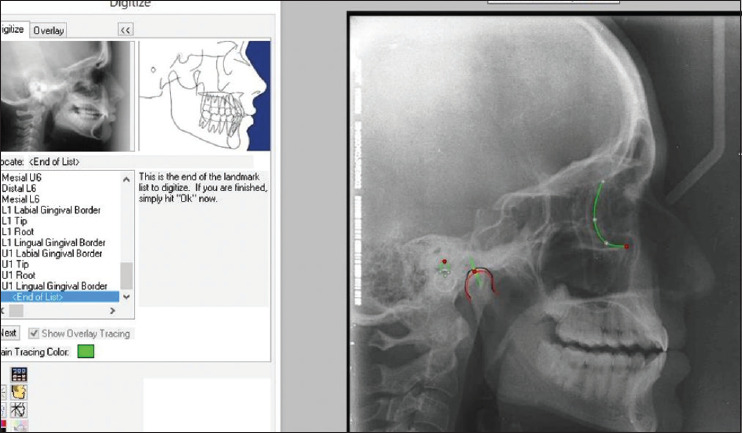

Materials and methods: Twenty-five dentate subjects participated in this study. Customized guides with calibrations at 2, 4, 6, and 8 mm were used to create protrusive interocclusal records at each increment. The HCG values derived from these records were set on a fully adjustable articulator (Denar D5A, Whip Mix Corp.). For control, standardized digital lateral cephalograms of each subject were taken in edge-to-edge and maximal intercuspal positions. These cephalograms were superimposed using Dolphin Imaging software (Dolphin Imaging and Management Solutions), allowing the determination of the cephalometric HCG angle by measuring the intersection between a line passing from the Condylion and the Frankfort horizontal plane. The HCG values from the articulator were compared with the cephalometric HCG values.